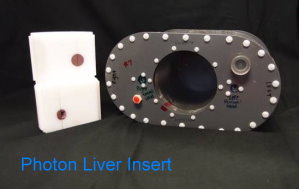

IROC Houston has developed a liver phantom. The phantom includes a liver with two targets, and 2 organs at risk. Click here for irradiation guidelines and forms for photon therapy, and click here for guidelines for proton therapy.